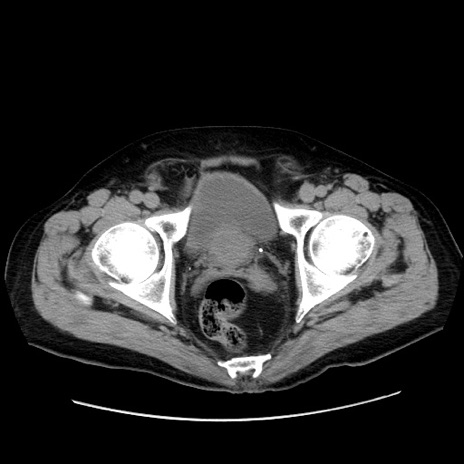

症例30(横断像)

【症例】80歳代男性

【主訴】臍周囲痛

【現病歴】約6時間前から臍下部痛が出現。次第に腹部膨隆・背部痛も生じてきたため来院。背部痛の場所は変化しない。

【身体所見】意識清明、BT 36.3℃、BP  131/87mmHg、P 87bpm、SpO2 100%(RA)、臍周囲自発痛・圧痛あり、反跳痛なし、自発痛部位に一致して板状硬あり、腹部膨隆、腸雑音減弱、CVA tenderness両側陰性。